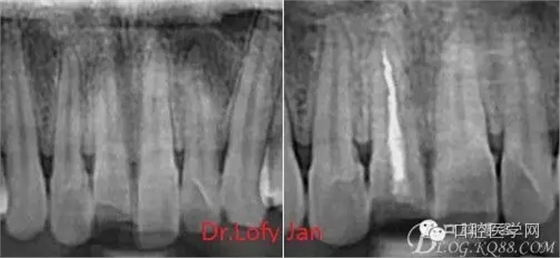

曲面斷層片在未試尖根管治療中的病例整理

前言:自己做的一些曲面斷層片在未試尖根管治療中的病例整理,發(fā)現(xiàn)問題很多包括自身的,技術(shù)的,還有設(shè)備的問題,予以總結(jié)整理并期待進(jìn)一步提高。

根管治療術(shù)是牙體牙髓疾病治療中最復(fù)雜和最關(guān)鍵的治療項(xiàng)目。根管充填材料抵達(dá)根尖、并能嚴(yán)密堵塞根尖孔,是確保根管治療效果的關(guān)鍵指標(biāo)。為了保證根管充填到位,醫(yī)生需要在術(shù)前照牙片以了解牙根根管的數(shù)量、彎曲程度和長(zhǎng)度,在術(shù)中有時(shí)需要插針照牙片來精確測(cè)量根管長(zhǎng)度,術(shù)后必須照牙片以確定是否根管充填到位,如果欠填或超填,就需要重新充填、重新照牙片確認(rèn),直到根管充填到位。所以,在患者接受根管治療時(shí)有時(shí)會(huì)反復(fù)照牙片。

病例分析:曲面斷層片在x線輔助診斷與檢查中目前大多數(shù)文獻(xiàn)和著作都建議只能作為初診拍片檢查手段,不能作為終末疾病的確診與手術(shù)療效的評(píng)價(jià)指標(biāo),臨床大部分中小型門診都因?yàn)樵O(shè)備不齊全導(dǎo)致信息偏差很大。